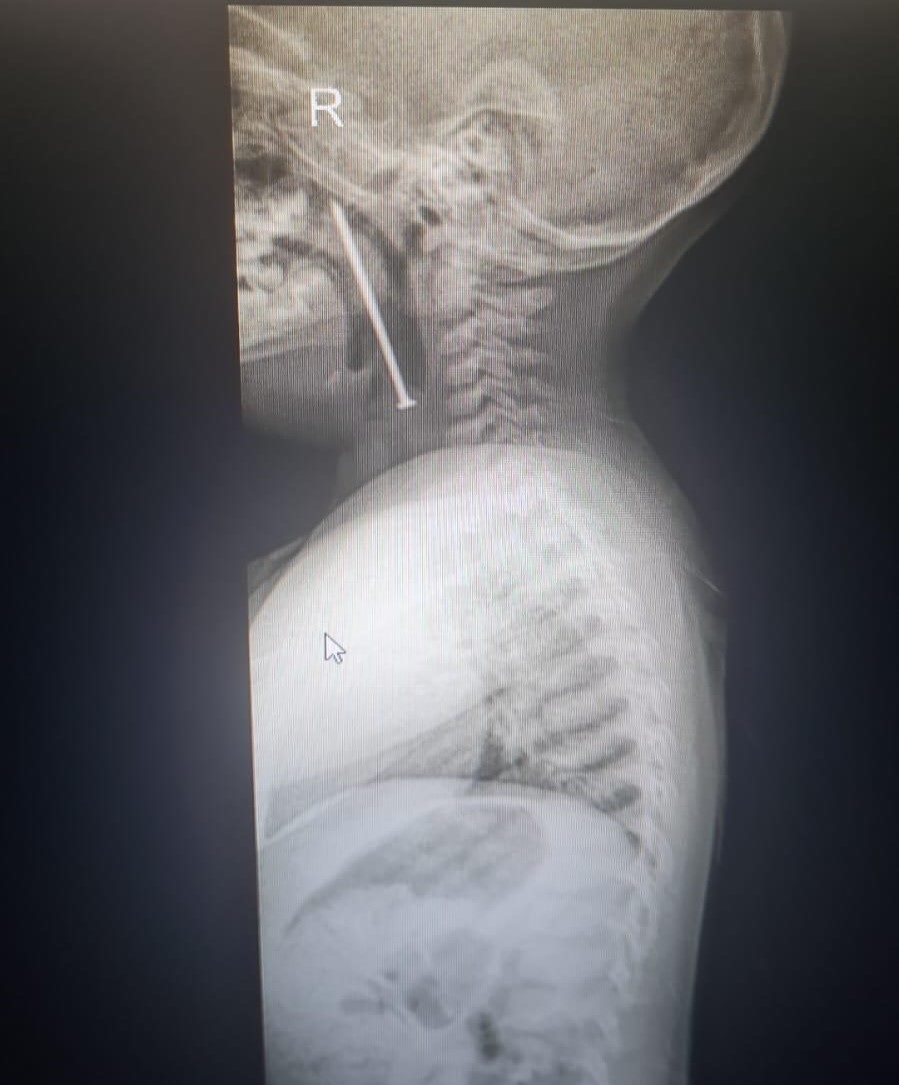

SDÜ Araştırma ve Uygulama Hastanesi Kulak Burun Boğaz Hastalıkları Anabilim Dalı Öğretim Üyesi Doç. Dr. Mehmet Emre Sivrice, çocuğun hastaneye gece saatlerinde getirildiğini ve çektikleri röntgende boğazında bir cisim olduğunu gördüklerini belirtti.

Doç. Dr. Sivrice, yapılan işlem ile ilgili olarak şu bilgileri verdi; “Hasta genel anestezi altında hazırlandı. Nefes borusunda yabancı cisim olması nedeni ile entübe edilmedi. Sedasyon altında yabancı cisim olduğu görüldü. Cismin sivri kısmı yumuşak damağa saplandığı diğer keskin ucunun da nefes borusuna kadar uzandığı izlendi. Bir tarafı sivri çivi saplandığı yerden kurtarılarak çıkarıldı. Hastamız sağlıklı bir şekilde taburcu edildi. Ailelerin özellikle bu yaşlardaki çocuklarda çok dikkatli olmaları gerekiyor. Bu tür vakalar ciddi hayati tehlike oluşturmaktadır.”